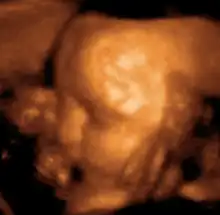

Medical ultrasound is an ultrasound-based diagnostic medical imaging technique used to visualize muscles, tendons, and many internal organs to capture their size, structure and any pathological lesions with real time tomographic images. Ultrasound has been used by radiologists and sonographers to image the human body for at least 50 years and has become a widely used diagnostic tool. The technology is relatively inexpensive and portable, especially when compared with other techniques, such as magnetic resonance imaging (MRI) and computed tomography (CT). Ultrasound is also used to visualize fetuses during routine and emergency prenatal care. Such diagnostic applications used during pregnancy are referred to as obstetric sonography. As currently applied in the medical field, properly performed ultrasound poses no known risks to the patient.[36] Sonography does not use ionizing radiation, and the power levels used for imaging are too low to cause adverse heating or pressure effects in tissue.[37][38] Although the long-term effects due to ultrasound exposure at diagnostic intensity are still unknown,[39] currently most doctors feel that the benefits to patients outweigh the risks.[40] The ALARA (As Low As Reasonably Achievable) principle has been advocated for an ultrasound examination – that is, keeping the scanning time and power settings as low as possible but consistent with diagnostic imaging – and that by that principle nonmedical uses, which by definition are not necessary, are actively discouraged.[41]